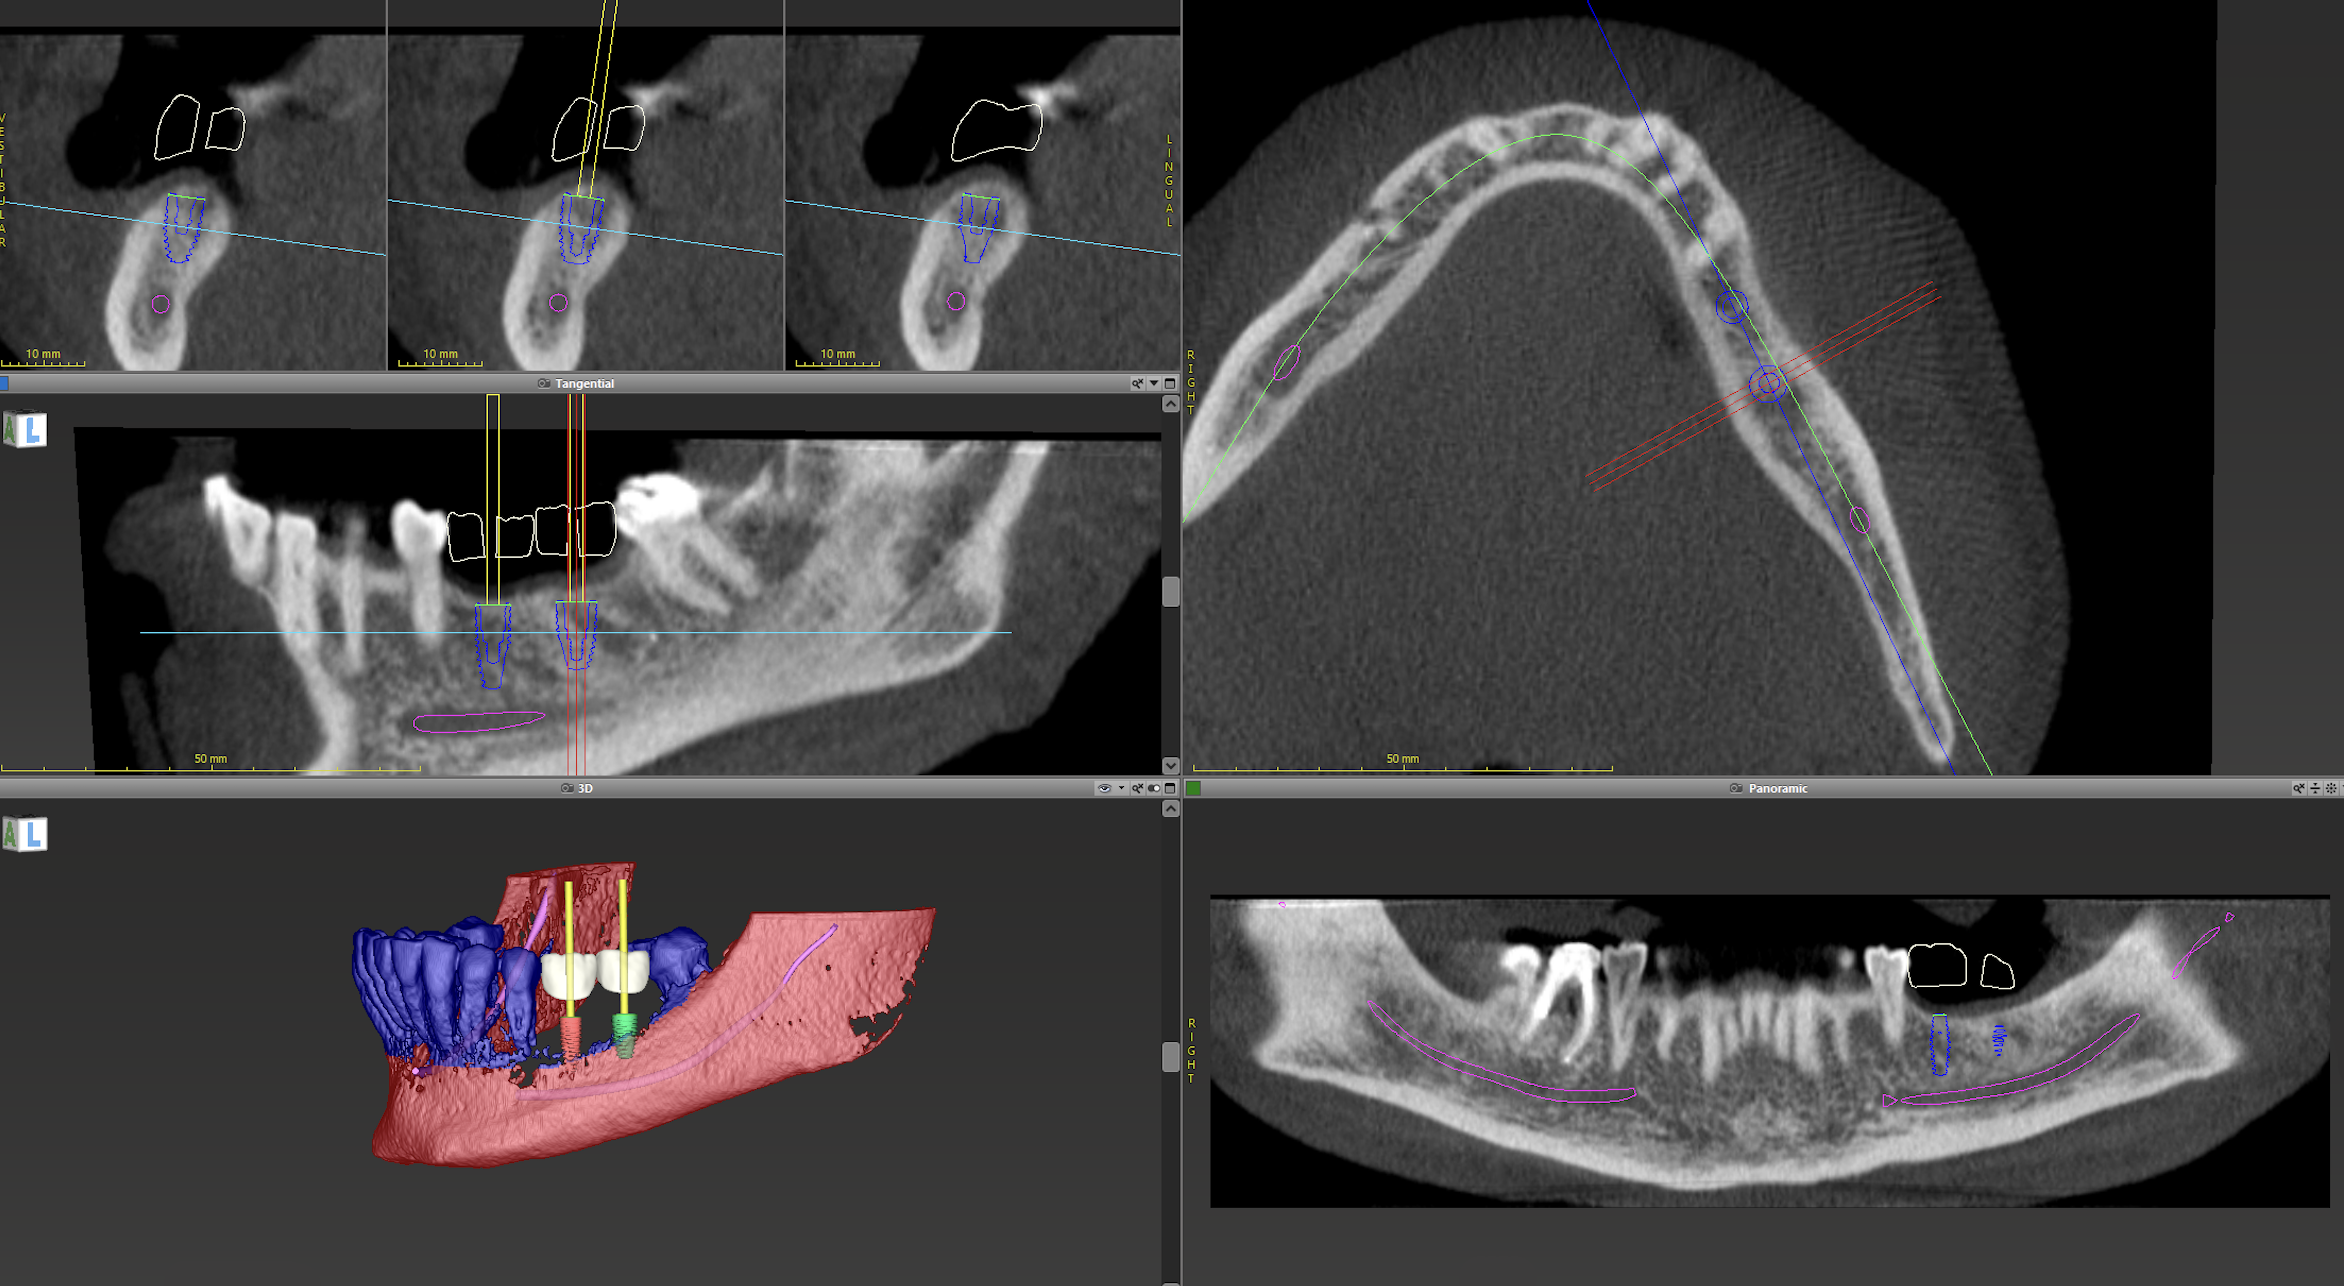

There are certain disciplines, i.e., implantology, that have embraced CBCT as key to treatment planning (see Figure 1). Future developments will likely expand the number of disciplines that regularly utilize CBCT for diagnosis and treatment planning. That will depend on future advances in limiting radiation exposure and greater availability of the technology. Unlike 2-dimensional radiography, for reasons of cost, availability, and the need for clarity as to which clinical situations would benefit from the information, CBCT radiography is not widely available in dental offices.

Figure 1: CBCT images as part of implant planning for a partially edentulous mandible

Images courtesy of Dr. David T. Wu, Harvard School of Dental Medicine.

1) Top left panel of 3 images: axial view of implant planning in the lower left mandible

2) Middle left panel: sagittal section - location of inferior alveolar and mental nerve in relation to implant position

3) Bottom left panel: segmentation and 3D rendering of teeth and implant position

4) Top right panel: occlusal view of mandible with implant position

5) Bottom right panel: panoramic projection with position of interior alveolar nerve and dental implant position